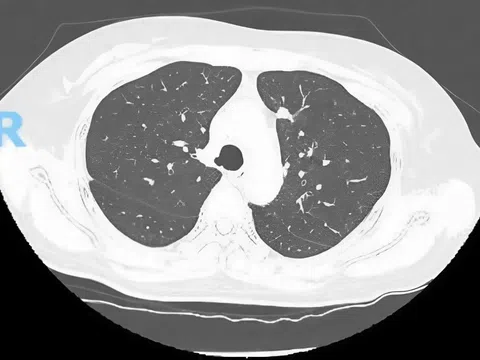

Ban đầu, chấn thương của nam tiền đạo có vẻ không quá đáng kể. Tuy nhiên, kết quả chụp phim ghi nhận mức độ tổn thương nghiêm trọng hơn dự đoán: gãy 1/3 dưới xương mác và đứt dây chằng Delta cổ chân.

Tổn thương này thường xảy ra khi khớp cổ chân bị xoay quá mức. Cụ thể, trong tình huống này, bàn chân sẽ bị xoay vào trong trong khi cẳng chân xoay ra ngoài, vượt quá giới hạn vận động của khớp, từ đó dẫn đến chấn thương.

Nguyên nhân chấn thương cổ chân có thể xuất phát từ hai yếu tố: tác động bên ngoài hoặc tự chấn thương. Trong trường hợp của Vĩ Hào, chấn thương xảy ra do động tác đổi hướng đột ngột trong lúc tập luyện, khi bàn chân vẫn còn tiếp xúc với mặt sân, khiến cổ chân bị xoắn vặn quá mức.

Nếu lực xoắn chỉ ở mức trung bình, tổn thương thường chỉ ảnh hưởng đến dây chằng. Tuy nhiên, khi lực tác động quá lớn, có thể gây tổn thương nghiêm trọng hơn như gãy mắt cá ngoài và đứt dây chằng Delta.

Chấn thương tự thân tuy có lực không cao so với chấn thương do tác động bên ngoài nhưng lại tạo ra tác động xoắn mạnh, dễ dẫn đến tổn thương kết hợp giữa xương và dây chằng vùng cổ chân.

Lý giải nhận định này, vị chuyên gia cho biết vùng cổ chân có một cấu trúc khớp quan trọng gọi là khớp gọng chày - mác, nơi xương sên bị kẹp giữa hai xương lớn của cẳng chân là xương chày và xương mác.

Để duy trì sự ổn định của khớp này, xương sên phải đủ vững chắc trong khi hệ thống dây chằng cần linh hoạt để hỗ trợ các hoạt động như đi lại, chạy nhảy. Khi khu vực này bị tổn thương, khả năng di chuyển sẽ bị ảnh hưởng nghiêm trọng, quá trình hồi phục cũng kéo dài và phức tạp hơn so với các chấn thương khác.